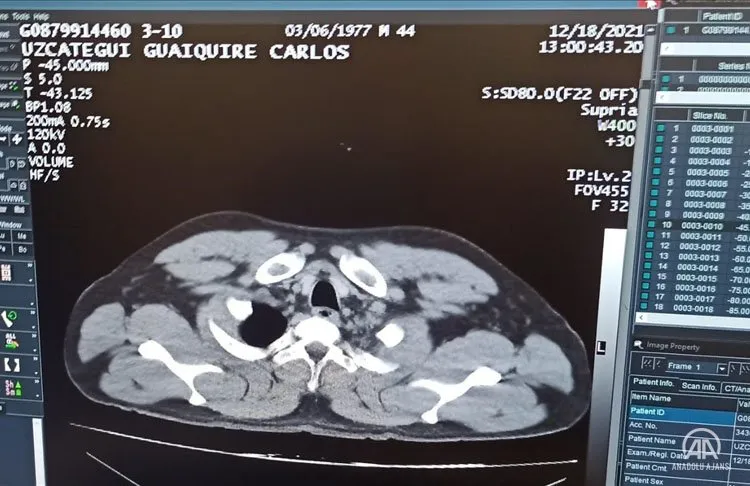

Tomografi kontrolünde de mide ve bağırsaklarda tespit edilen kapsüllerin ameliyatla alındığı şüpheli, taburcu olmasının ardından adliyeye sevk edildi.